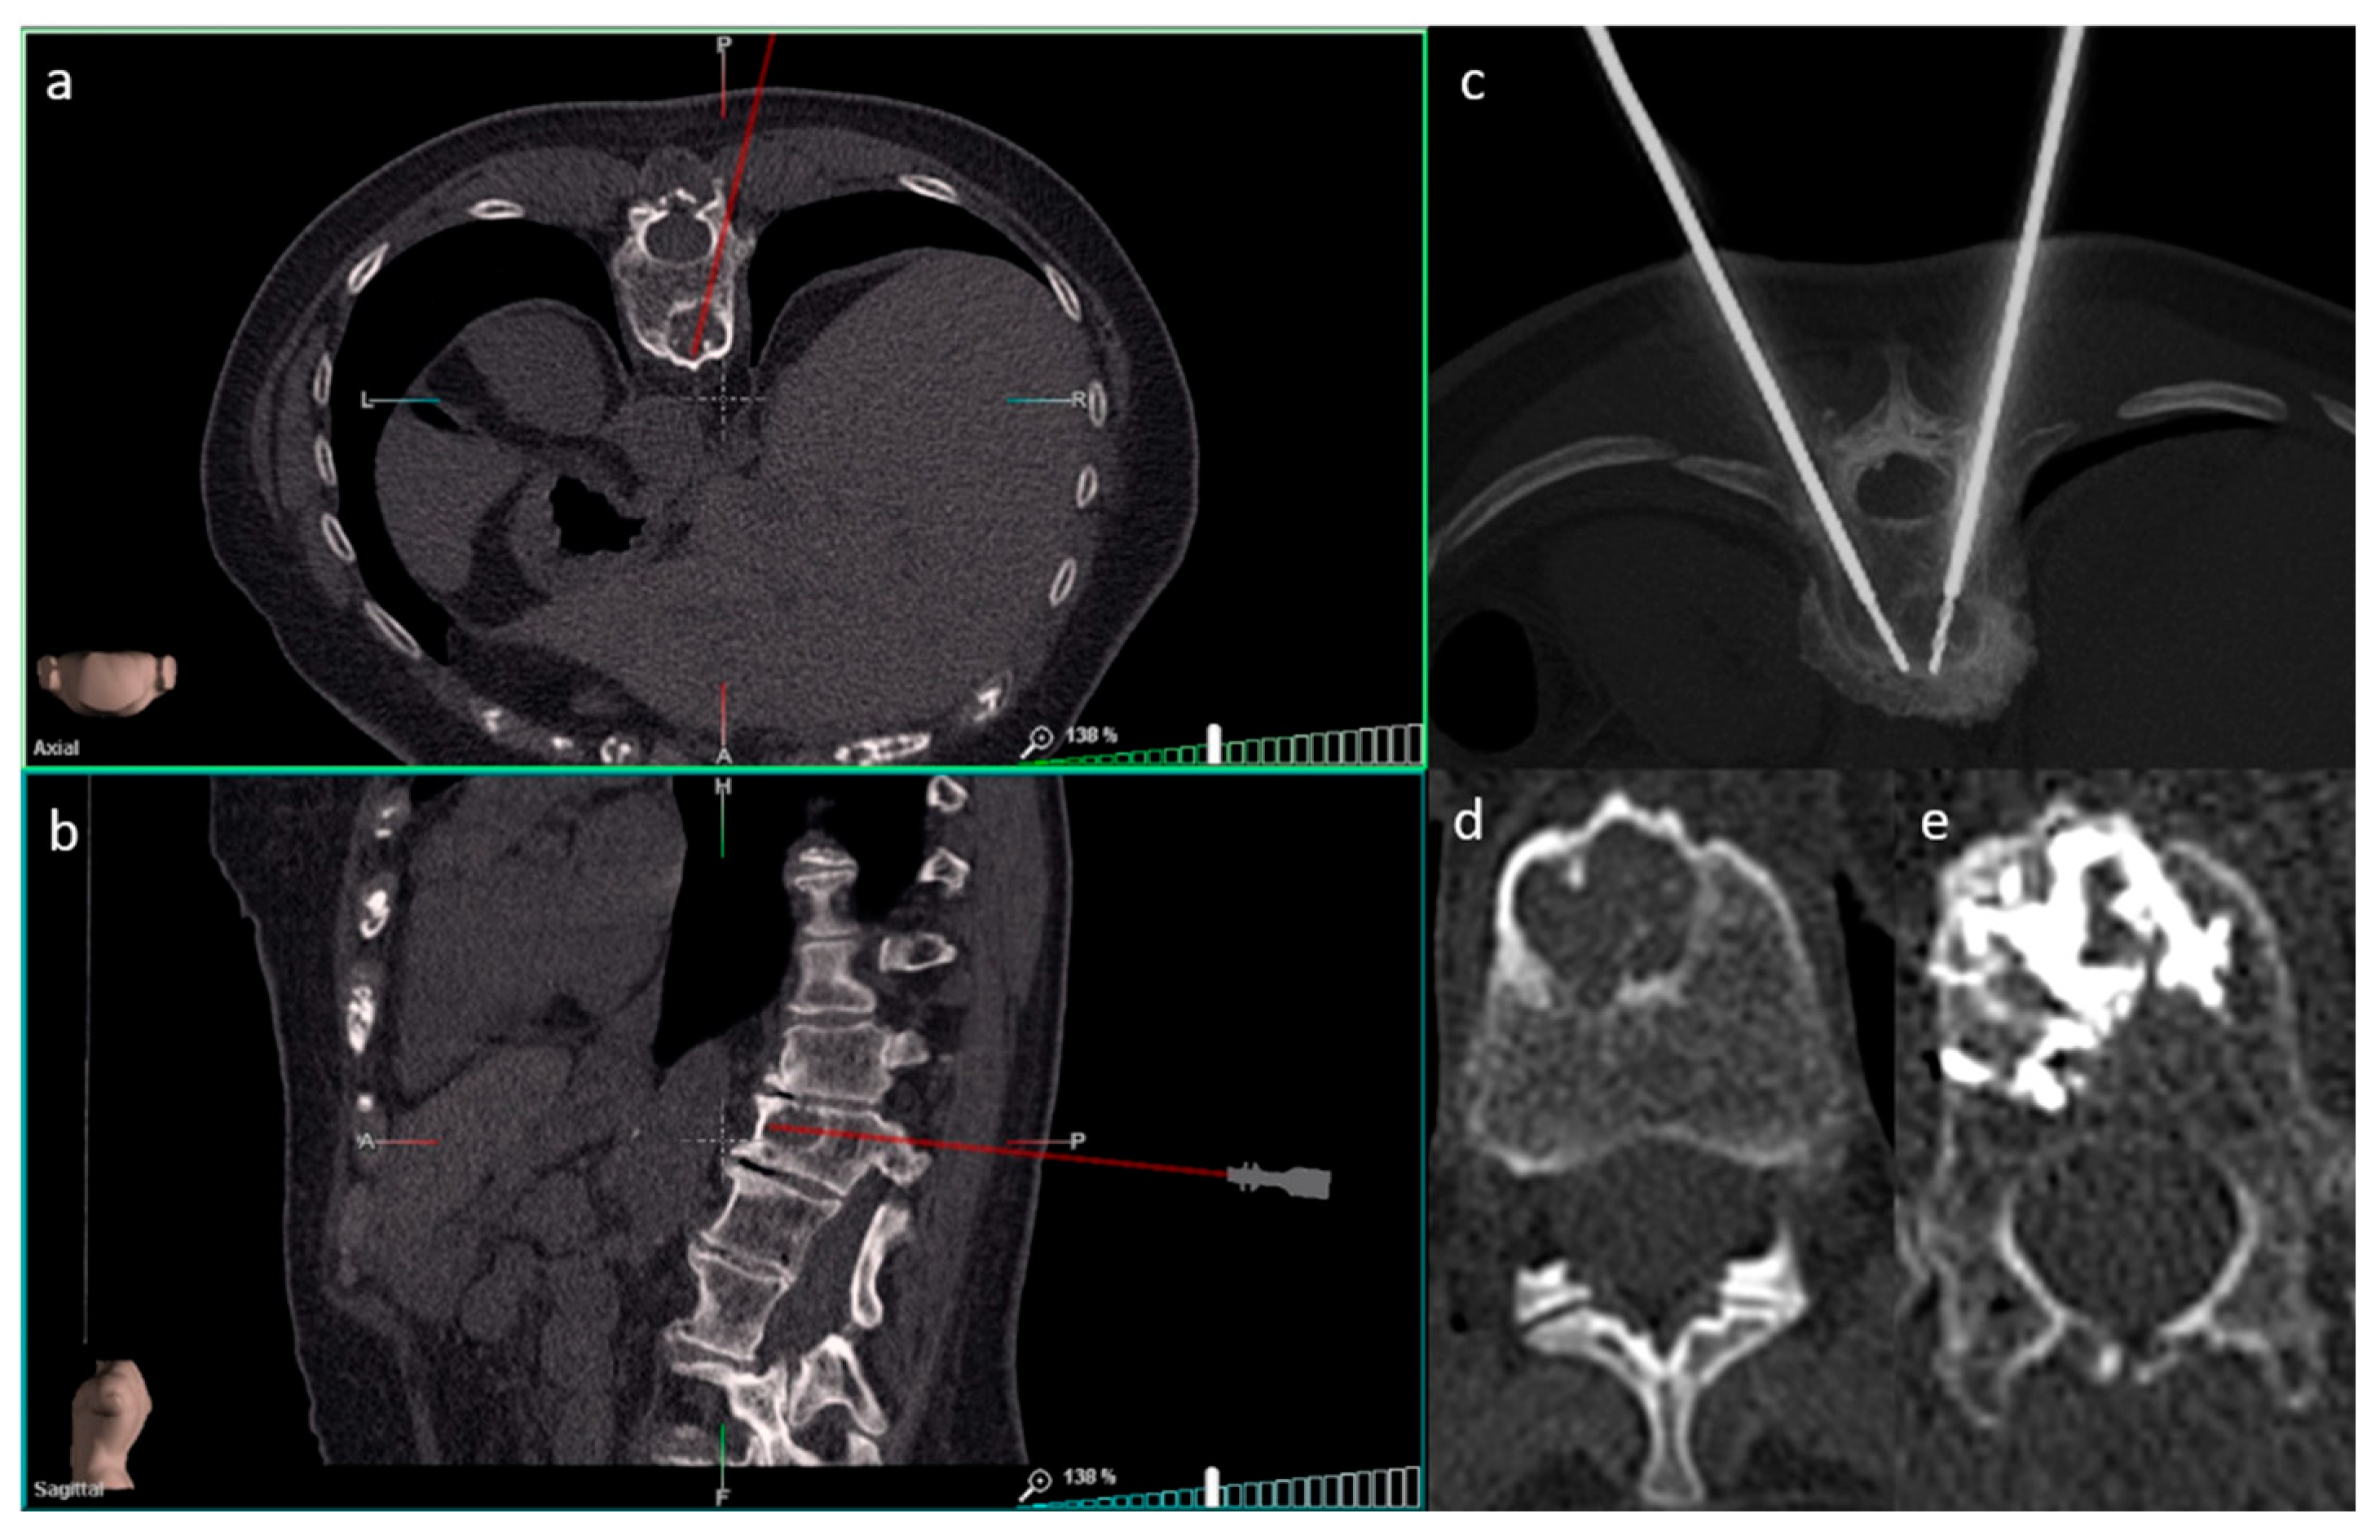

2.2.2. Ablations

2.3. SIRIO Augmented Reality Navigation System